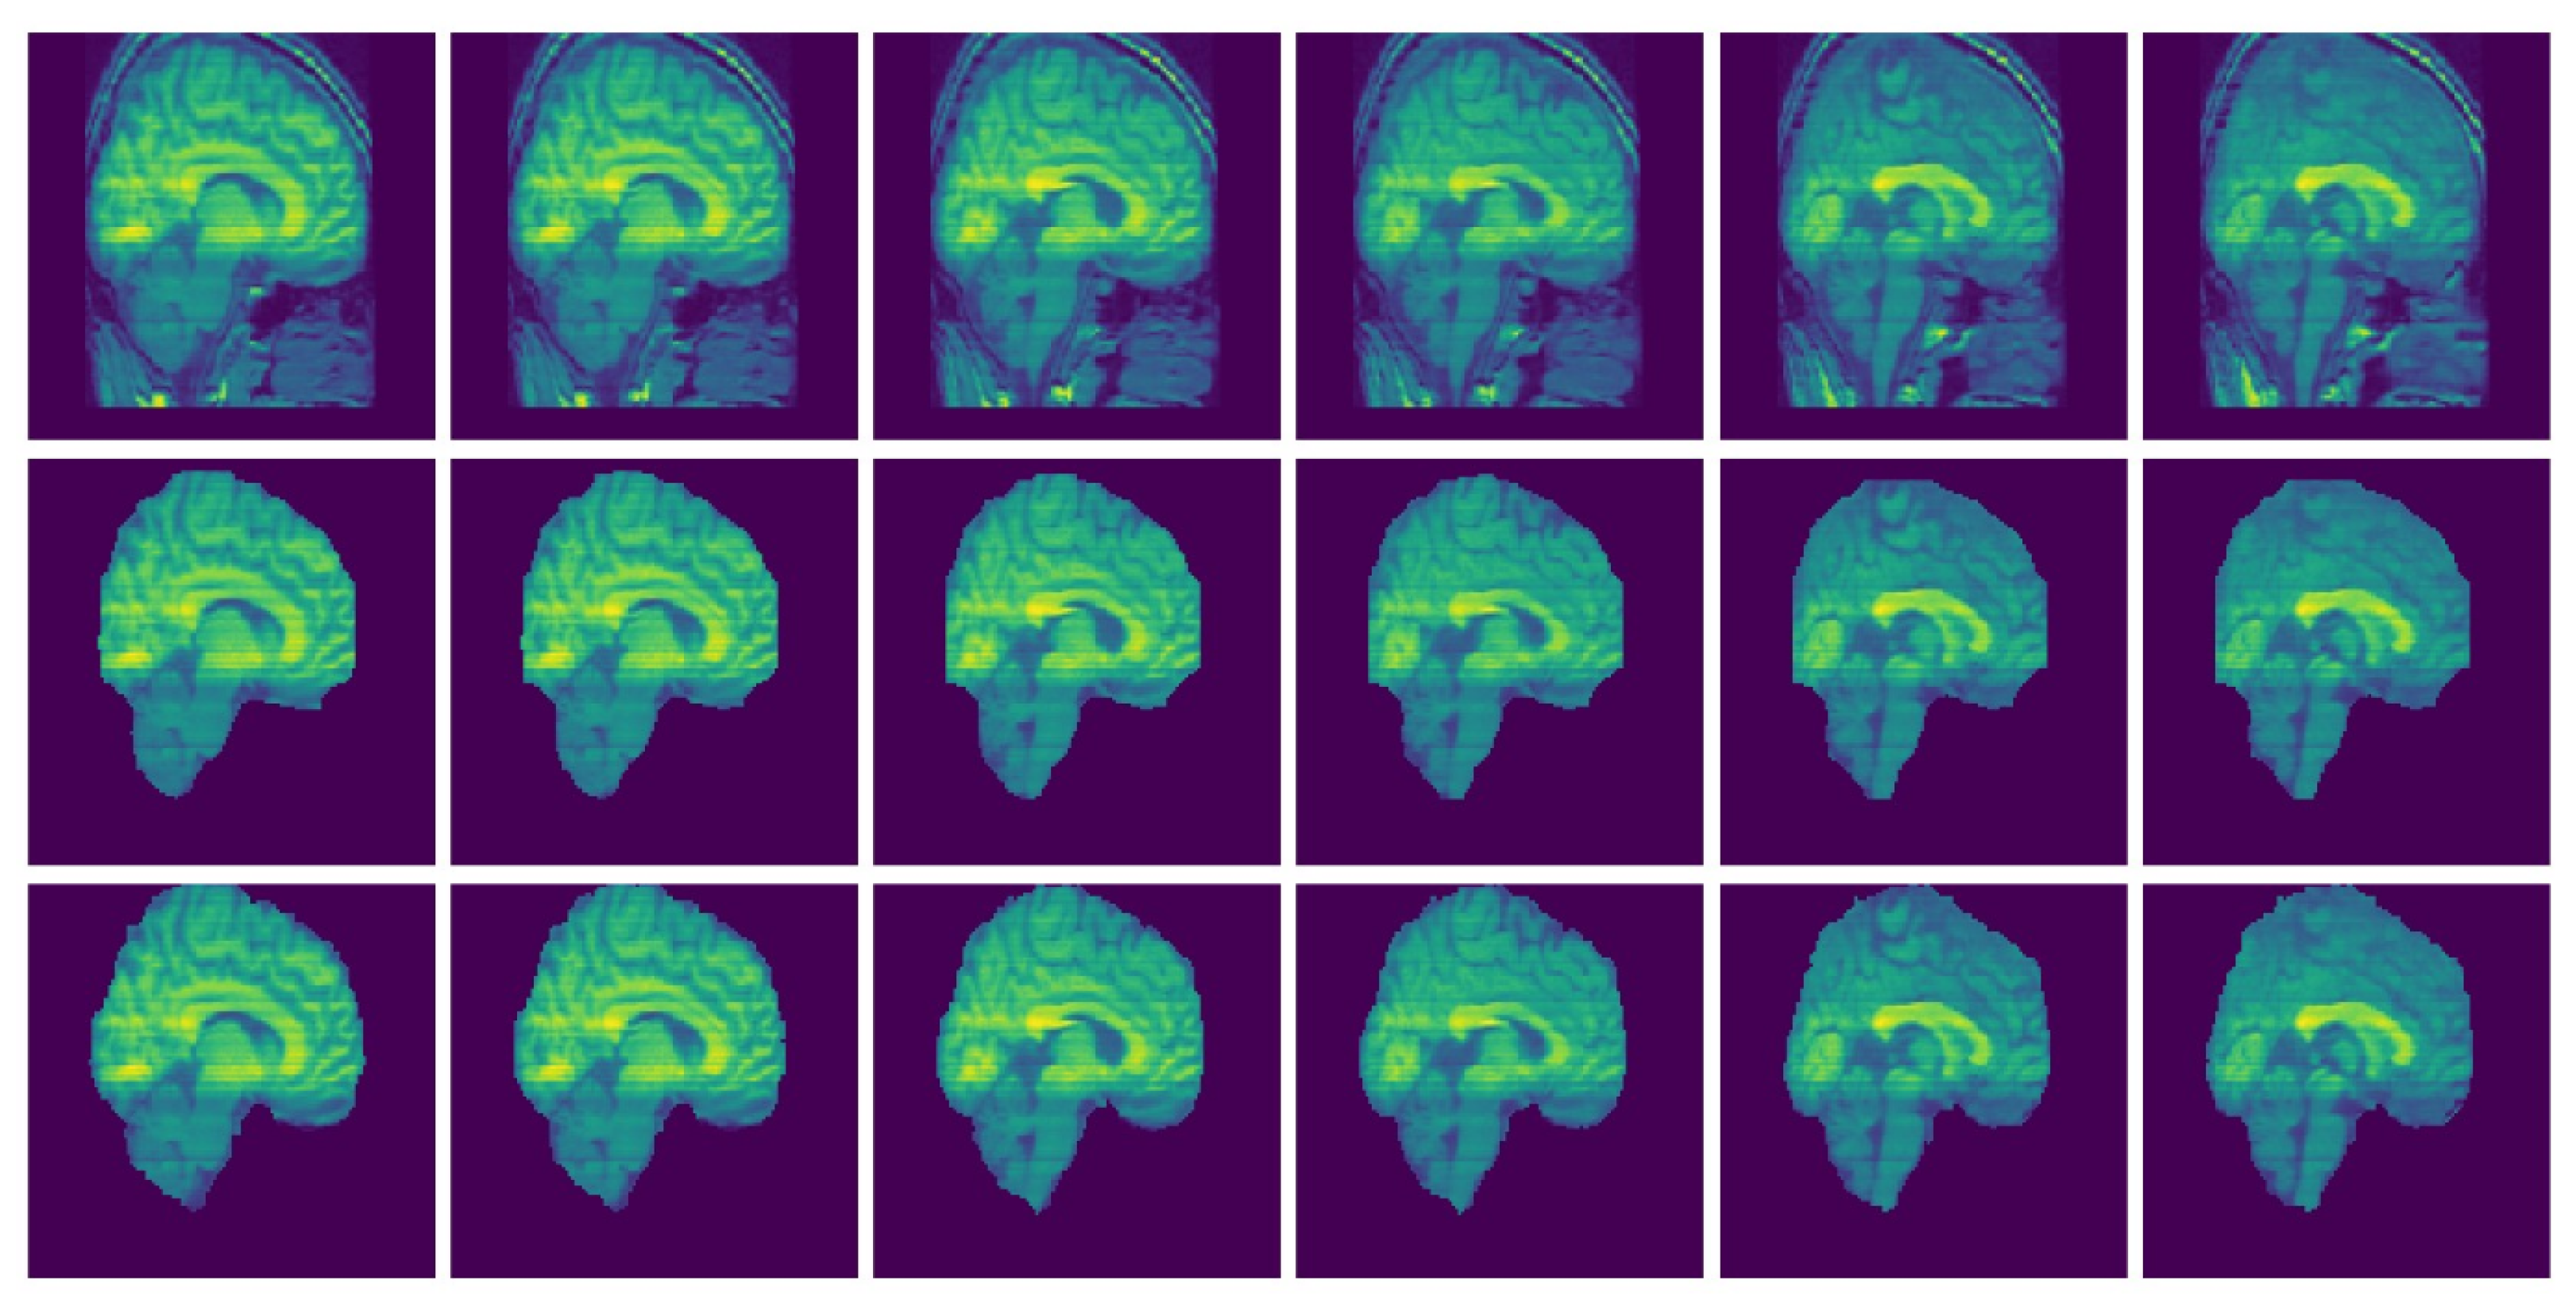

Figure 9 and Figure 10 present examples of a visual comparison of 2D slices segmented from two different subjects from IBSR and OASIS data sets, respectively. Notice that for Figure 9, the original sagittal sections show that some parts of the 3D head were cut. Figure 10 also present representative sagittal sections from a single subject. Since the proposed approach depends on sampling points within different regions, tuning the parameters for extracting the brain from the two compared MRI volumes (Figure 9 and Figure 10) can differ significantly.

Figure 9.

Selected MRI slices (IBSR data set): Sagittal MRI plane segmented brain. Row one: Input images, Row two: Predicted brain and Row three: Ground truth brain.

Figure 10.

Selected MRI slices (OASIS data set): Sagittal MRI plane segmented brain. Row one: Input images, Row two: Predicted brain and Row three: Ground truth brain.

Figure 9 and Figure 10 show experimental result of one subject from IBSR and OASIS, respectively. The challenging part is to sample within the non-brain tissues because some parts of the brain and non-brain tissues have been removed (see row one in Figure 9). Some points sampled from the non-brain tissues are likely to be taken from the brain when is applied. For Figure 9 and Figure 10, and .